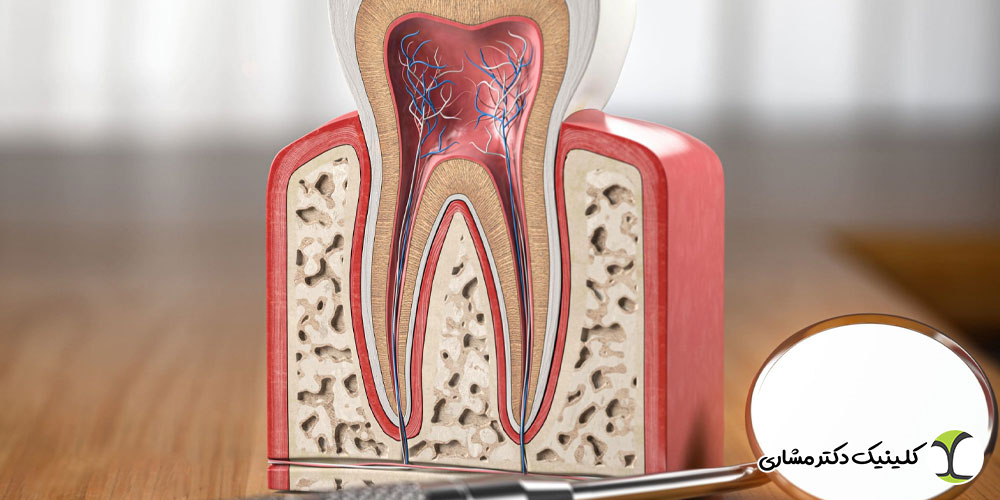

گوشت دندان (پالپ) شامل عصب، رگهای خونی و بافت های زنده است. زمانی که این بخش دچار التهاب، عفونت یا آسیب جدی میشود، بیمار علائم مشخصی را تجربه میکند. اگر این علائم نادیده گرفته شوند، درمان ممکن است پیچیده تر شود و حتی منجر به از دست رفتن دندان گردد.

پیش از بررسی علائم، لازم است بدانیم درمان ریشه دقیقاً زمانی لازم میشود که پالپ دندان ملتهب، عفونی یا دچار نکروز (مرگ بافت) شده باشد. عوامل مختلفی میتوانند باعث چنین آسیبی شوند:

درمان ریشه باعث میشود:

- عفونت حذف شود

- درد و التهاب برطرف گردد

- دندان برای سالها قابل استفاده بماند

- از گسترش عفونت به استخوان و سایر دندانها جلوگیری شود